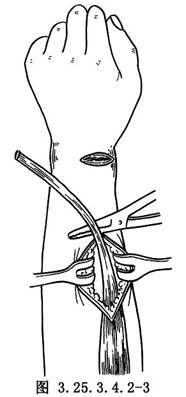

先在手背第3掌骨基底部做橫切口,顯露橈側伸腕短肌腱,並自止點切斷,從前臂橈側距橈骨莖突8~10cm縱切口中抽出,轉向掌側(圖3.25.3.4.2-3)。